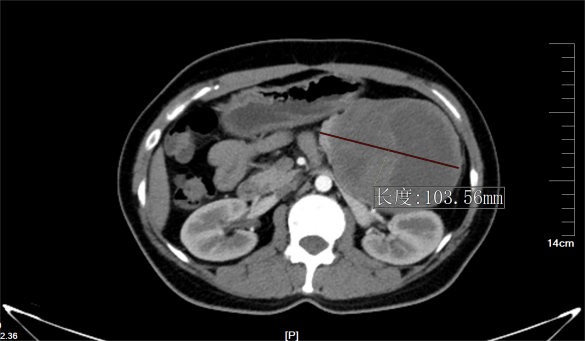

古主任接诊后,为甘女士进行了细致的检查后,结合影像学检查结果分析,考虑患者胰腺体尾部占位为胰腺实性-假乳头状瘤可能,肿瘤巨大,压迫周围脏器组织,侵犯包绕脾动静脉,需行外科手术切除治疗。

▶ 胰体尾部囊实性巨大占位的CT影像

古主任介绍此次3D腹腔镜下胰体尾联合脾脏切除术有两大大挑战。一是风险高,病灶位于胰体尾,挤压到左肾、胃、脾等器官,侵犯包绕脾动静脉,其周围集中了腹腔重要的血管、器官,术中分离困难,出血风险大,损伤任何一个组织都可能导致术后出现严重并发症。二是操作空间小,由于患者病灶为胰腺体尾部囊实性巨大占位,最大直径超过10cm,病灶基本充满左上腹,行微创操作,手术视野的暴露及操作的空间很小,对术者手术操作技巧要求更高。